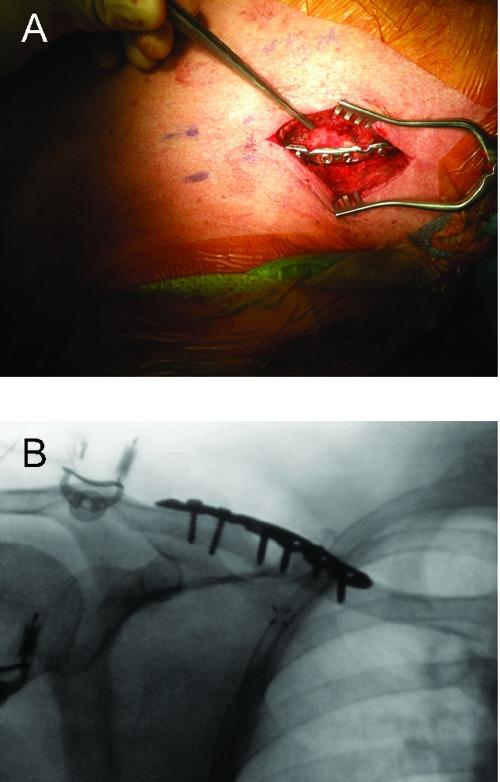

Clavicular eosinophilic granuloma causing adult shoulder pain.

Rare Tumors. 2013 Mar 1;5(1):e8. doi: 10.4081/rt.2013.e8. Print 2013 Feb 11.